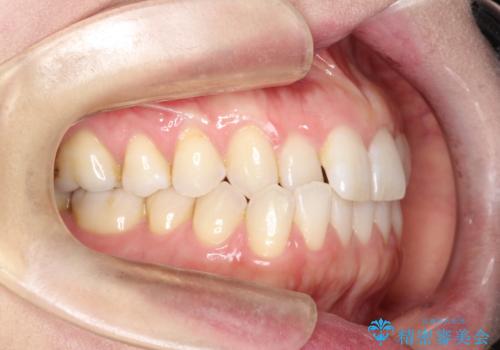

上の歯と下の歯が反対にかんでいる インビザラインによる目立たない矯正

- 右上の前から2番目と3番目の歯が内側に引っ込んでしまっているのを主訴に来院されました。

右上の2番目と3番目のはが前後反対にかんでしまっている状態でした。

内側に引っ込んでいる歯も、インビザラインにてしっかり外側に動かすことができます。